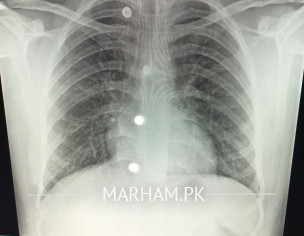

hello kindly koi doctor guide kar Sakta ha ma medicine use kar rha ho Jo picture send ki ha but mocus throat Sy nai ja rhi koi medicine mocus ko relief nai dy rhi anybody help

dear doctor sab kindly Jo chest x-ray share kiya ha AP bta sakty kya masala h